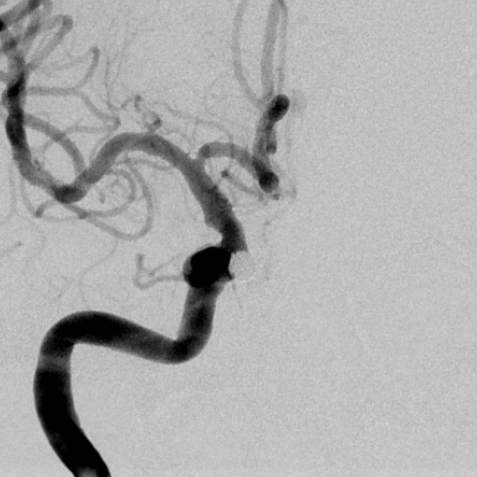

啥也别说了,赶紧去做脑血管造影备治疗吧,结果发现颅内一个炸弹💣(颅内动脉瘤),而且长在一个不太容易破裂的部位(床突旁),形状也不太规则,上面还有一个细长的小泡(破裂点),破裂机制:这个破裂小口,多次小量出血,通过反复的脑脊液循环大部集聚到了腰大池,出现了颅内几乎看不到啥异常而腰大池内为血性不凝脑脊液的巨大反差,血液在蛛网膜下腔进一步刺激神经根,才导致了脖子疼和腰疼~~~,但是,这是脑动脉瘤反反复复破裂出血导致的哦,细思极恐………